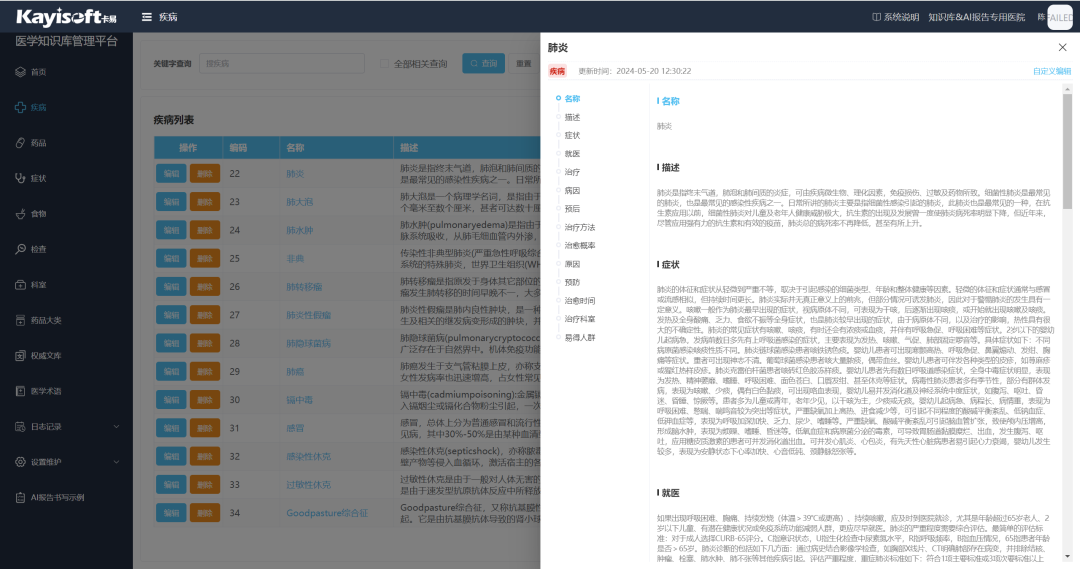

名词解析:点击蓝色字体可查看知识库名词解析,有助于患者更好地理解自己的病情、治疗方案以及预防措施,从而做出明智的健康决策。根据患者的病情和检查结果,推送相关的健康教育内容,例如疾病知识、预防措施、治疗方案等。

智能影像专病种库与知识库平台